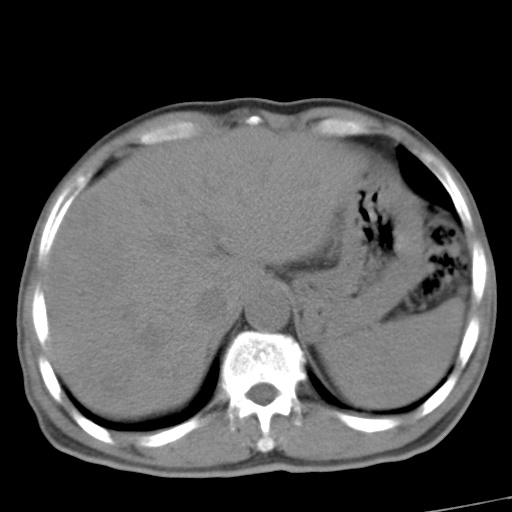

标题: CT17975:请求会诊。男、57岁。上腹部胀痛2天。临床诊断:糜 [打印本页]

标题: CT17975:请求会诊。男、57岁。上腹部胀痛2天。临床诊断:糜

肝脏多发类圆形低密度影,考虑肝脏转移瘤,肝胃韧带一淋巴结肿大,原发?胃癌?

考虑胃癌并肝脏及腹膜后淋巴结转移;不排除淋巴瘤。

肝内转移瘤,腹腔及腹膜后淋巴结转移。